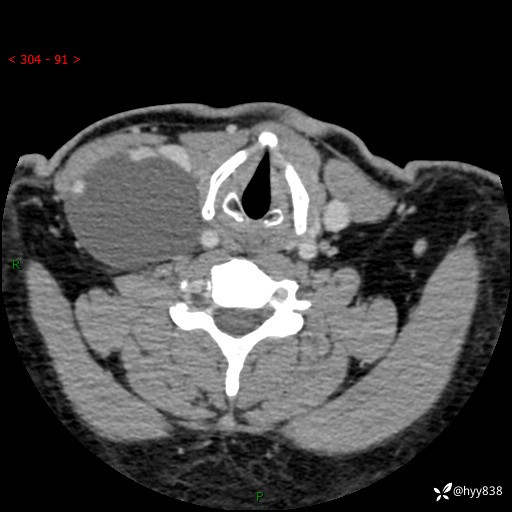

颈部CT平扫+增强